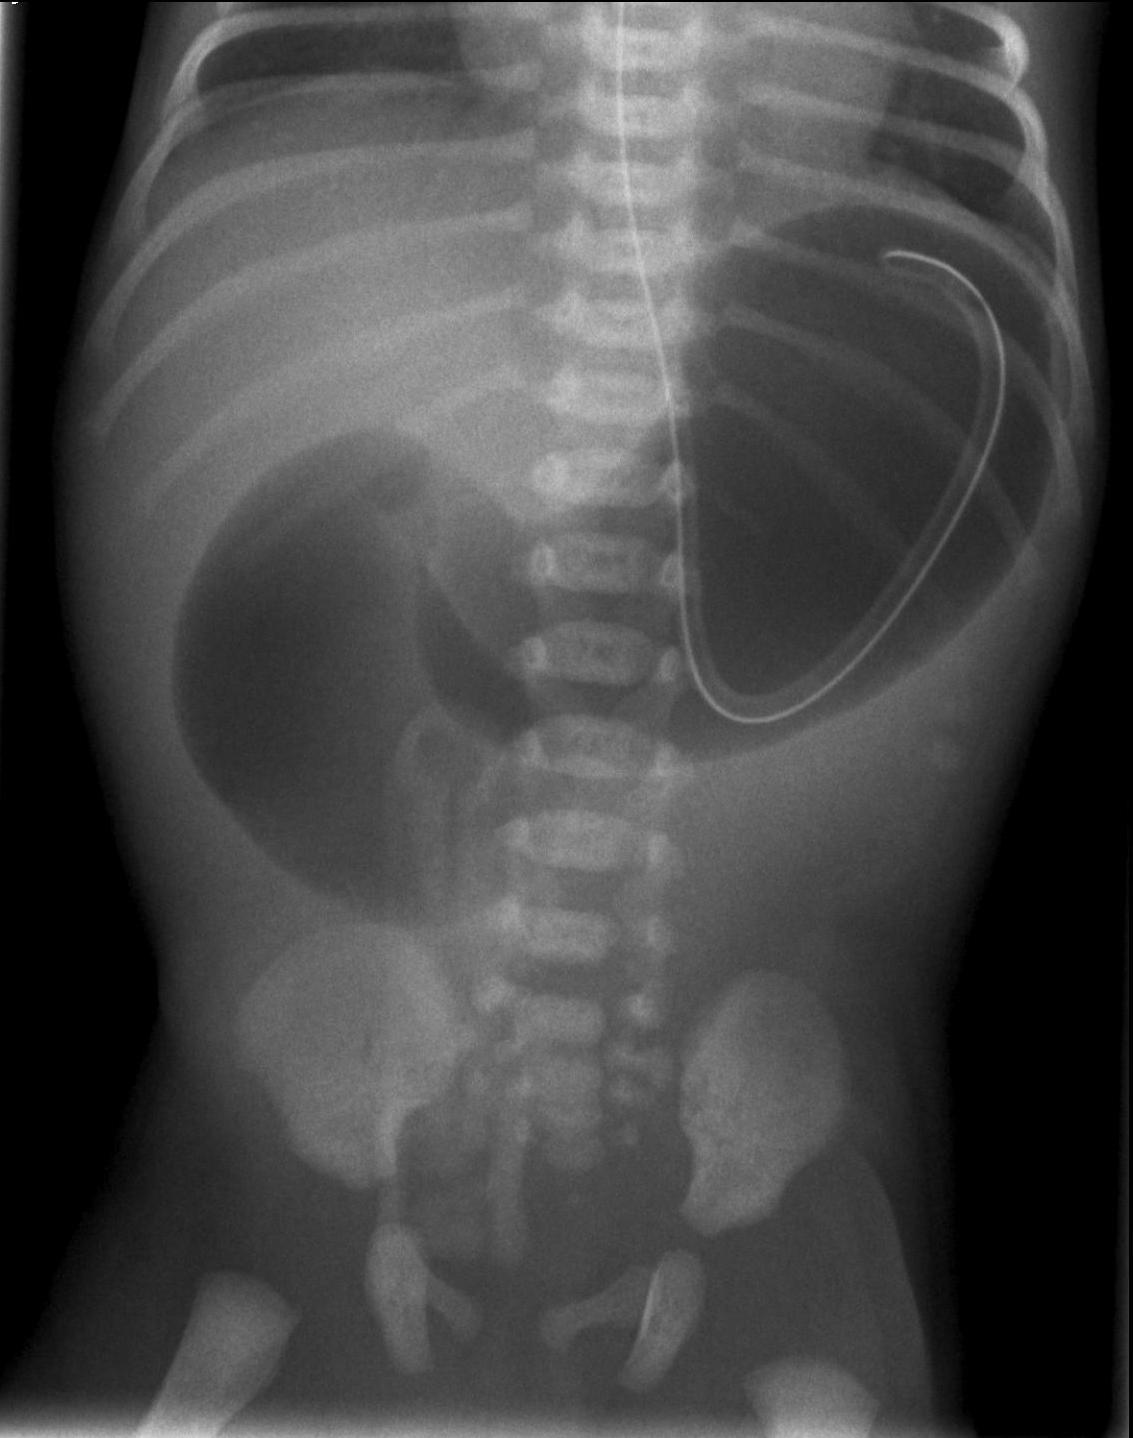

16. “Non-used”, narrow colon. Newborn, meconium ileus

Meconium ileus occurs in 10% of children with cystic fibrosis (CF), and almost all of meconium ileus cases are a result of CF disease. It is characterized by vomiting and abdominal distention, as the meconium cannot be defecated. On plain abdominal radiograph the intestines are distended without any air-fluid levels due to the adhesive nature of meconium. Colon enema examination with water soluble contrast material will show a micro-colon in which the meconium will cause contrast filling defects resembling small pearls. Contrast material that reaches the terminal ileum, and the repetition of the enemas can sometimes solve the ileus.